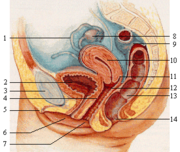

Z pohledu biologie ženské pohlavní orgány zahrnují rozmnožovací systém, kdežto druhotné pohlavní znaky se vyvinuly jen pro přilákání partnera nebo výživu a výchovu dětí. Většina netransexuálních žen má ve 46. chromozomálním páru dva chromozomy X (karyotyp 46,XX), ale zhruba každá tisící má tři (47,XXX ) a jedna z 2 500 jen jeden (45,X).

1. vejcovody, 2. močový měchýř, 3. stydká kost, 4. bod G, 5. klitoris, 6. močovod, 7. pochva, 8. vaječníky, 9. tračník, 10. děloha, 11. poševní klenba, 12. děložní hrdlo, 13. konečník, 14. anus